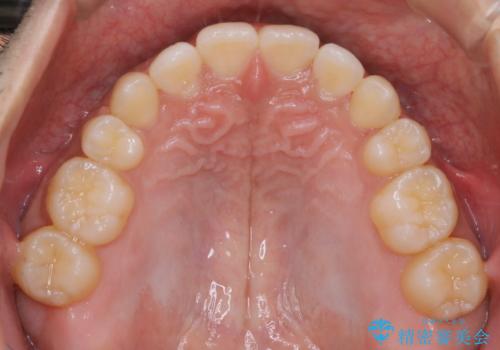

インビザライン単独でここまでできる!!抜歯矯正

1日20時間以上、正しくインビザラインを使用して頂いたおかげで、ワイヤーに切り替えることなく矯正治療を終了することが出来ました。周囲からも歯並びがすごく綺麗になったと言われたのことで大変ご満足いただけました。